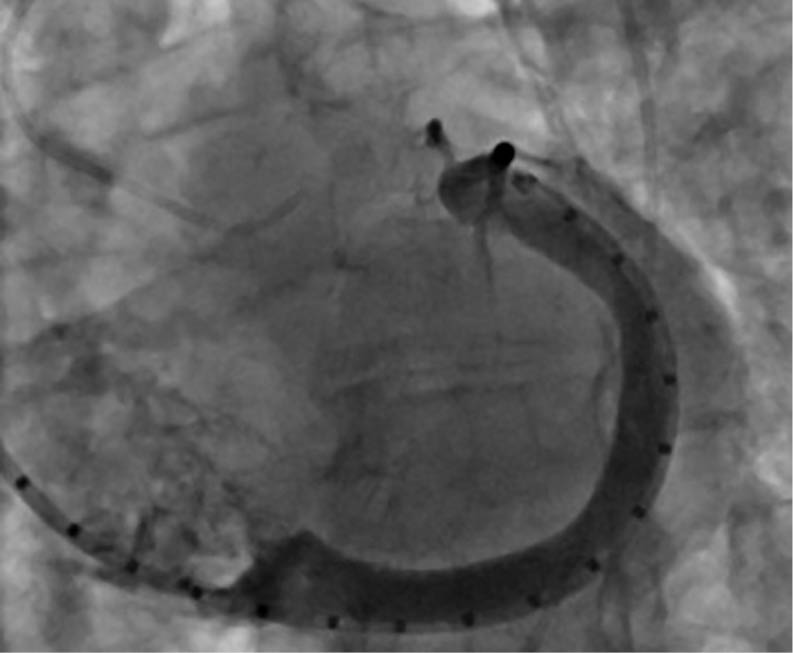

Abbildung 3b: intraprozedurales „Sizing“

unter der Fluoroskopie

Prozedur

Die Implantation eines 60-mm-Carillon®-Systems erfolgte unter fluoroskopischer und TEE-gestützter Kontrolle nach vorheriger intraprozeduraler Größenauswahl und Anpassung in Analgo-

sedierung. Die Implantation verlief komplikationslos. Eine angiographische Kontrolle schloss eine relevante Kompression des RCX und der RCA aus. Die Interventionsdauer betrug 45 Minuten, die Durchleuchtungszeit 11 Minuten.